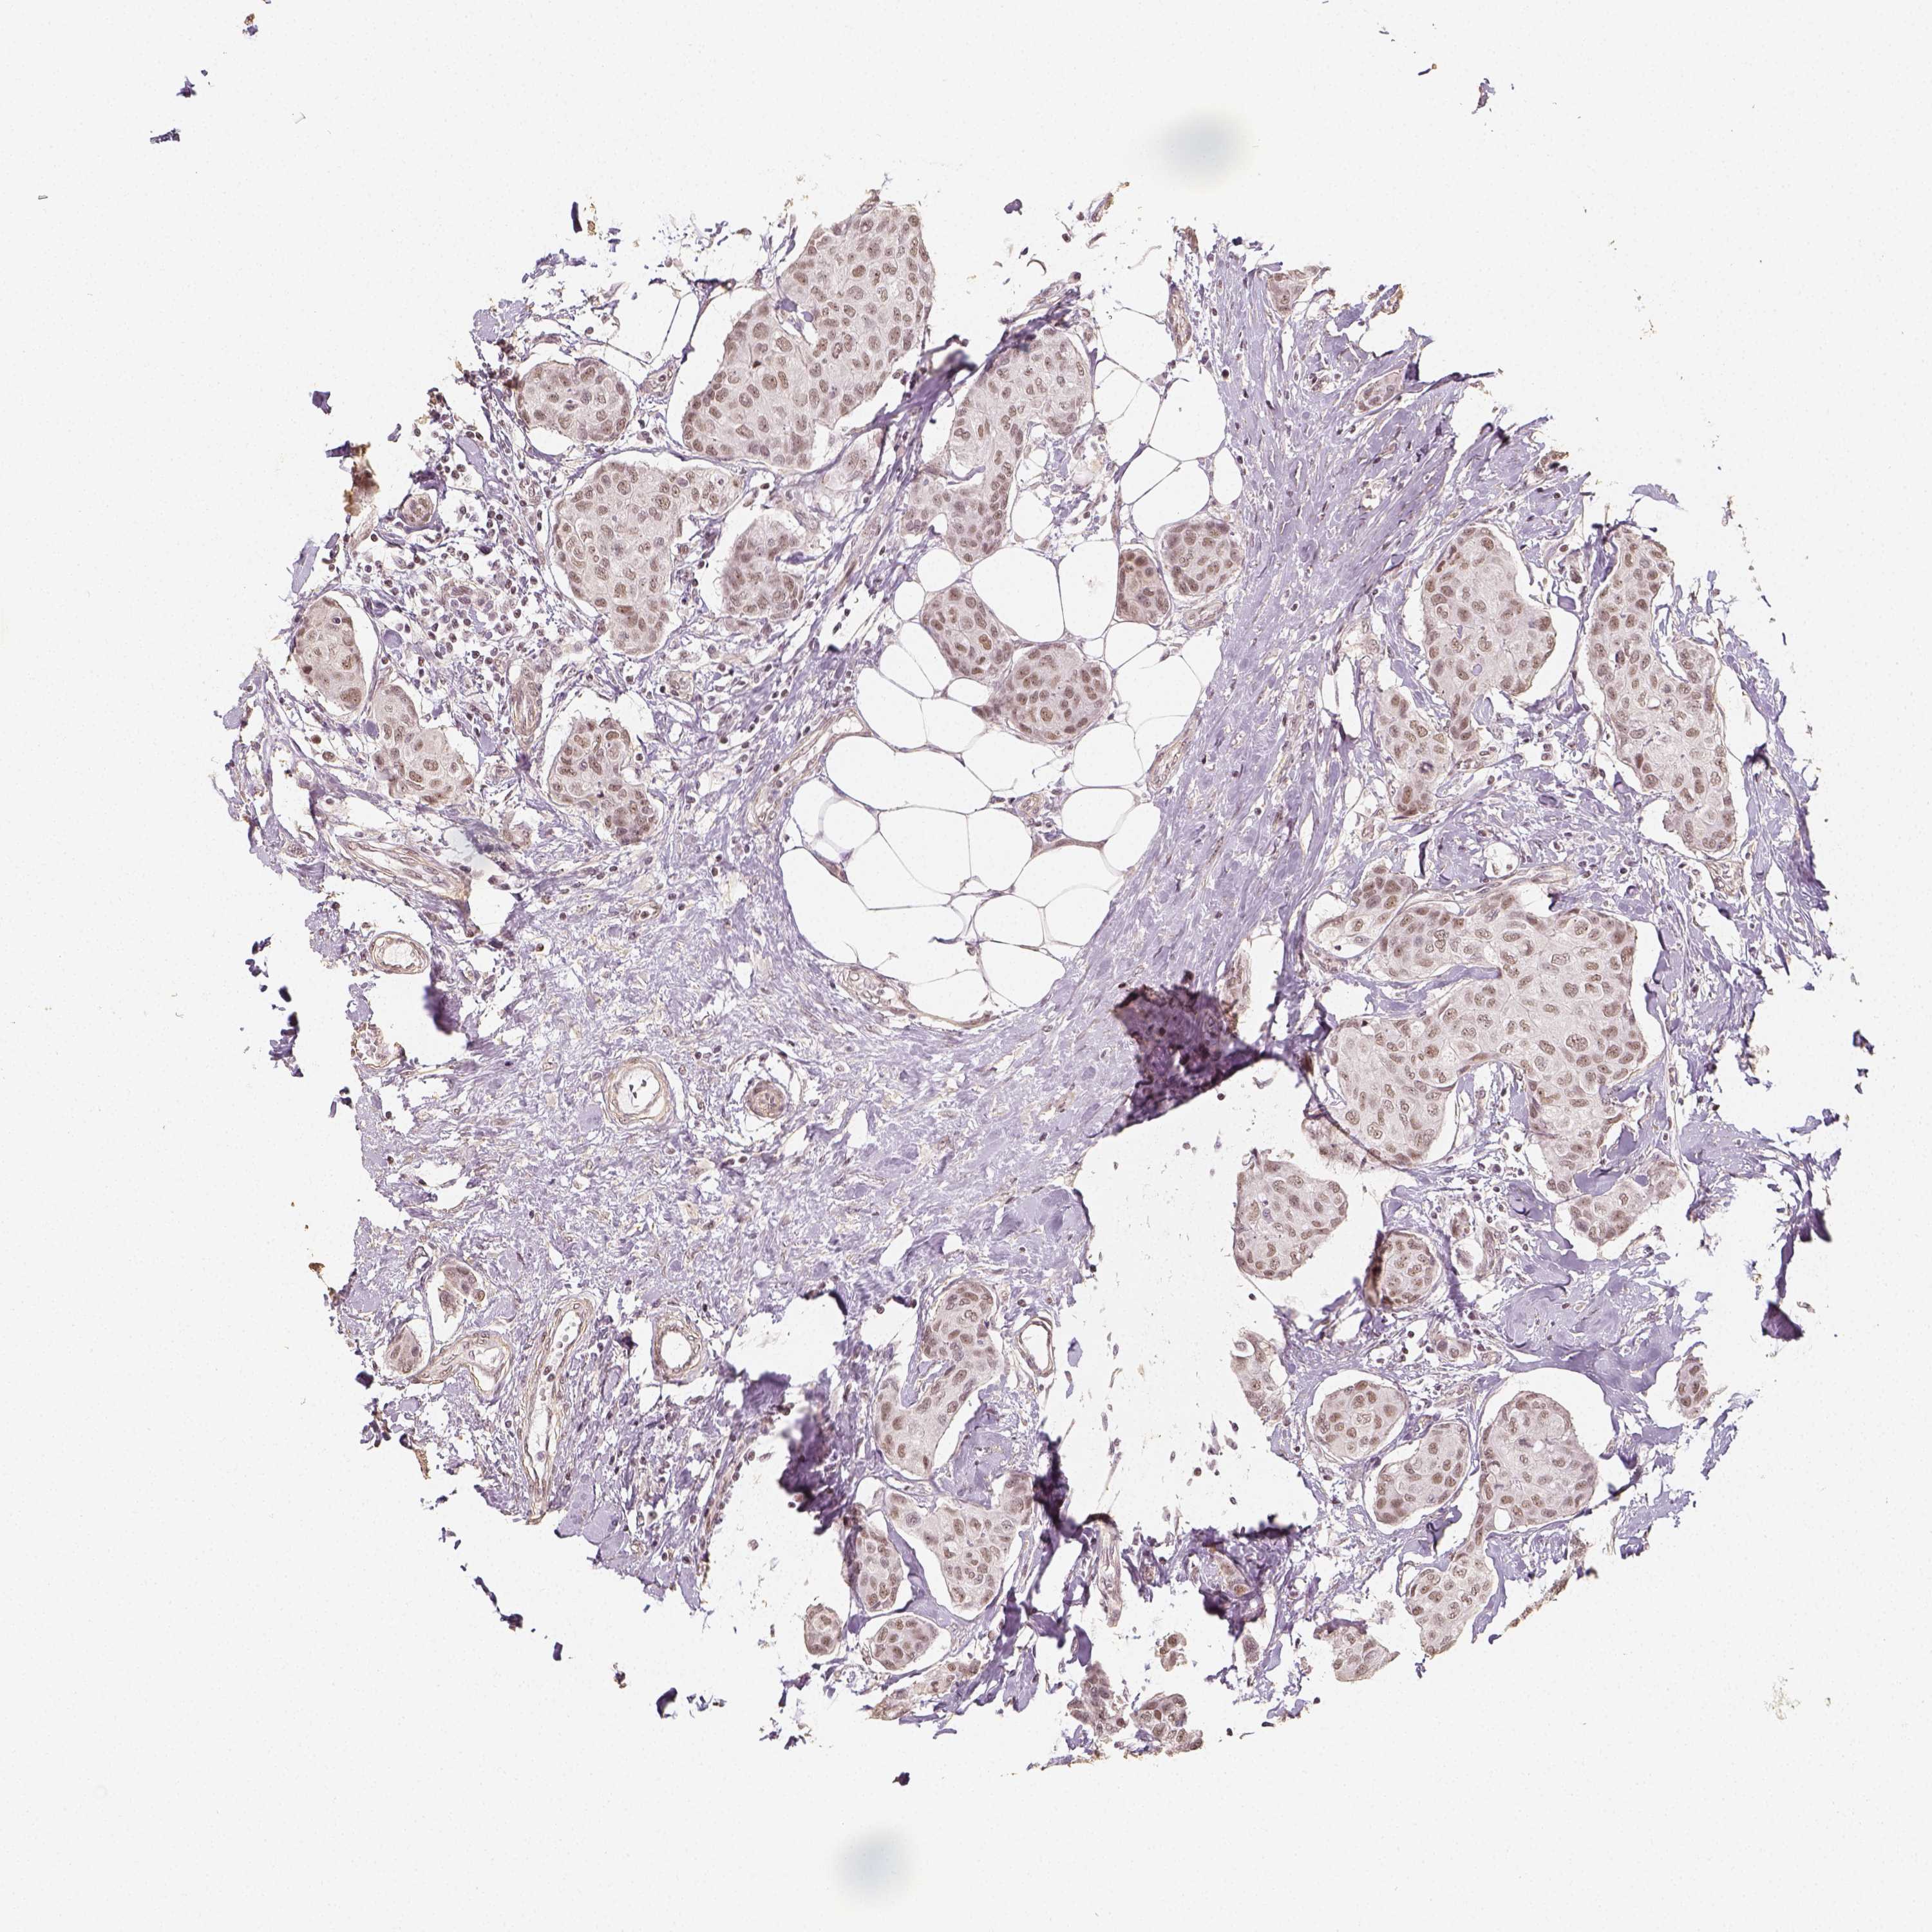

CANCER BREAST CANCER Show tissue menu

BRCA TCGA BRCA VALIDATION PROTEIN EXPRESSION